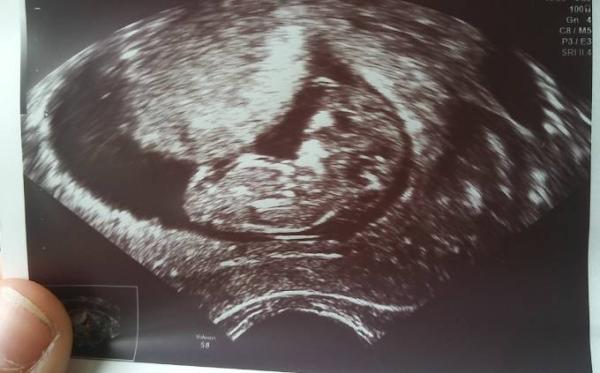

Oh yeeeah hab endlich meinen MuKiPass Kanns noch garnicht glauben Die 'Kleine' war beim us nicht gerade bestens gelaunt, und wollte mich wohl ärgern Jedesmal wenn es ein süßes bild geworden wäre und mein mann ganz begeistert den monitor angesehen hat drehte sie sich um, oder weg. Tja wenns so bleibt werden die nächsten jahre lustig Aaaber sie entwickelt sich so prächtig das ich auf den 04.01. vordatiert wurde Wäre der geb von der zukünftigen godi Liebe grüße und toi toi toi bei mir ist die morgenübelkeit samt Erbrechen weg

Super! Freut mich für dich! Hatte Montag auch US da war mein Wurm 3,2 cm groß. Und Meineids fruchthülle sieht genau so aus, wie bei dir hatte mein Bild sein können. Wie groß ist euer Wurm? Lg

Haha ist ja cool 3,8cm ssl Und was glaubst du was ihr bekommt? Hab so ein gefühl das es ein mädchen wird

Wow was für ein tolles Bild!! Ein richtiger kleiner Mensch Jetzt bin ich neidisch, ich darf erst in 3 Wochen wieder zum US...

Herzlichen Glückwunsch zu diesem tollen Termin. Da ist man echt erleichtert Und p.s.: ich finde irgendwie auch, dass es wie ein Mädchen aussieht